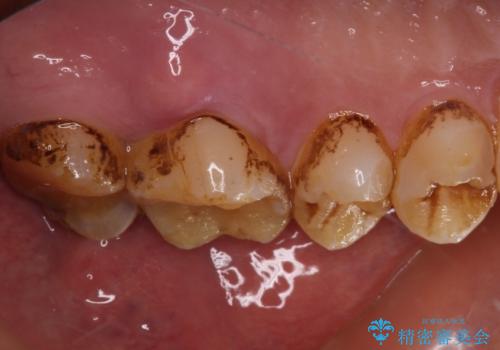

根管治療後に、歯根にまで及んでしまった破折部分を適切な位置に変更するため、歯槽骨の削除を伴う外科処置を行い、その後補綴治療を行うこととしました。

強い咬合力により歯が破折したため、補綴物は歯へのダメージの最も少ないゴールドクラウンを選択しました。